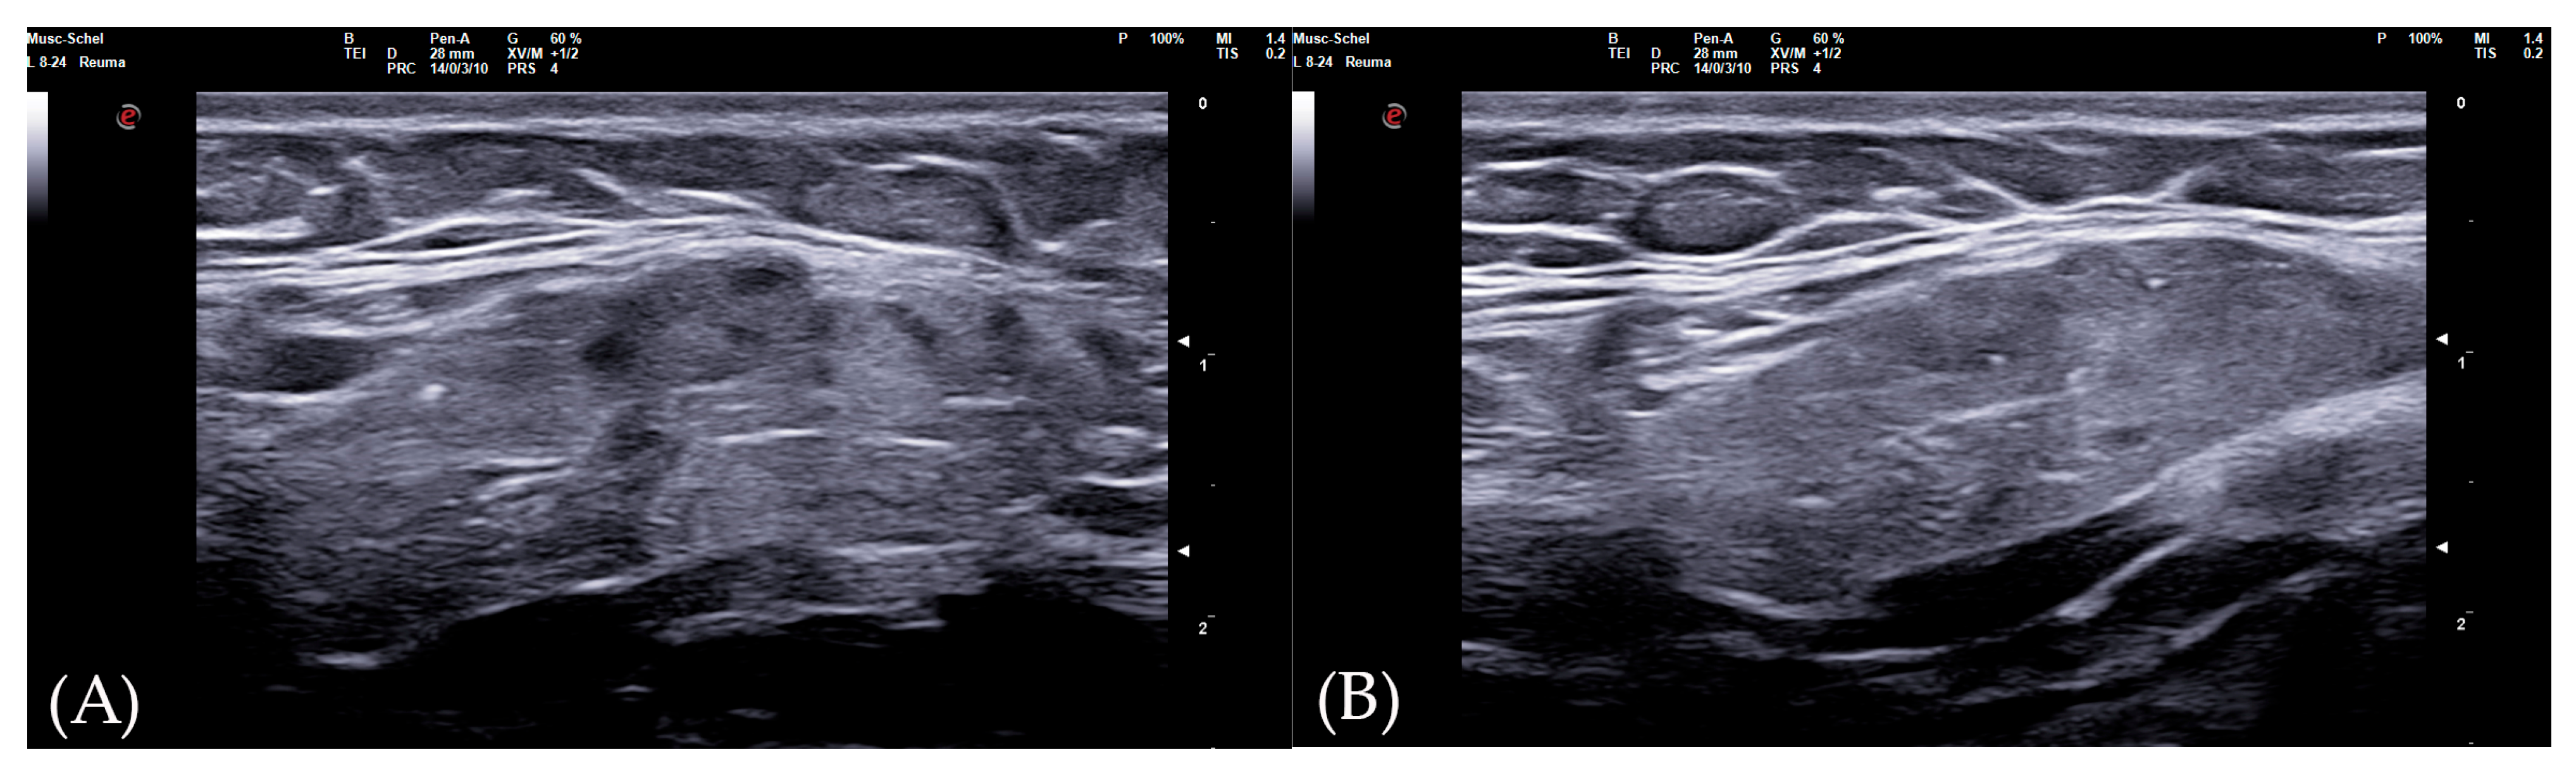

The diagnostic accuracy of the global SGUS score (sum of SGUS scores of all four glands) to diagnose SS was comparable with those of the parotid and submandibular glands on one side. A mild SGUS asymmetry between the two sides can be observed (Figure 5). Moreover, as some patients could have unilateral complaints or show focal glandular enlargement with high risk of lymphoma, a global view of all four glands should be preferred. However, SGUS in only one side might be taken in consideration in the case of previous mono-lateral surgery or radiotherapy without reducing diagnostic accuracy.

This study has several limitations. Specifically, the study was conducted in a context of real clinical practice, so an assessment of intra- and inter-operator agreement is lacking. However, our diagnostic performance data are comparable with previous results [13,14,28]. Due to the same reasons, another limitation is lack of complete immunological data of SS patients. Moreover, no patient was classified as affected from secondary SS, preventing us from evaluating the diagnostic performances of SGUS in this subset. The only patient with peripheral synovitis (see Figure 5) could not be diagnosed with anything other than primary SS. In any case, previous studies demonstrated no significant difference in SGUS appearance between primary and secondary forms of SS [29].

Figure 5. Submandibular glands in seronegative primary Sjogren syndrome. Female 57-year-old patient with peripheral symmetrical synovitis (some proximal inter-phalangeal and metacarpal-phalangeal of hands), sicca syndrome with positive Schirmer test, negative autoimmunity (ANA−, Ro-SSA−, La-SSB−, rheumatoid factor/ACPA−), positive labial biopsy for Sjogren syndrome, and type 1 diabetes mellitus. A coronal oblique scan over submandibular glands (8–24 MHz linear probe) shows a mild asymmetry on SGUS appearance: in the left side (A), moderate inhomogeneity with some hypo-anechoic areas occupying the superficial portion of gland (SGUS-OMERACT score = 2), whereas in the right side (B) SGUS shows mild inhomogeneity of the submandibular gland without hypo-anechoic areas (SGUS-OMERACT score = 1). The SGUS score of parotids was 2 on both sides. In this seronegative patient, only labial biopsy could define Sjogren syndrome diagnosis, but its SGUS global score of 7 had a 100% of specificity for the diagnosis.